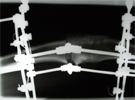

Post

Op

Opening wedge osteotomy through CORA hinge at the concave cortex

Correction obtained